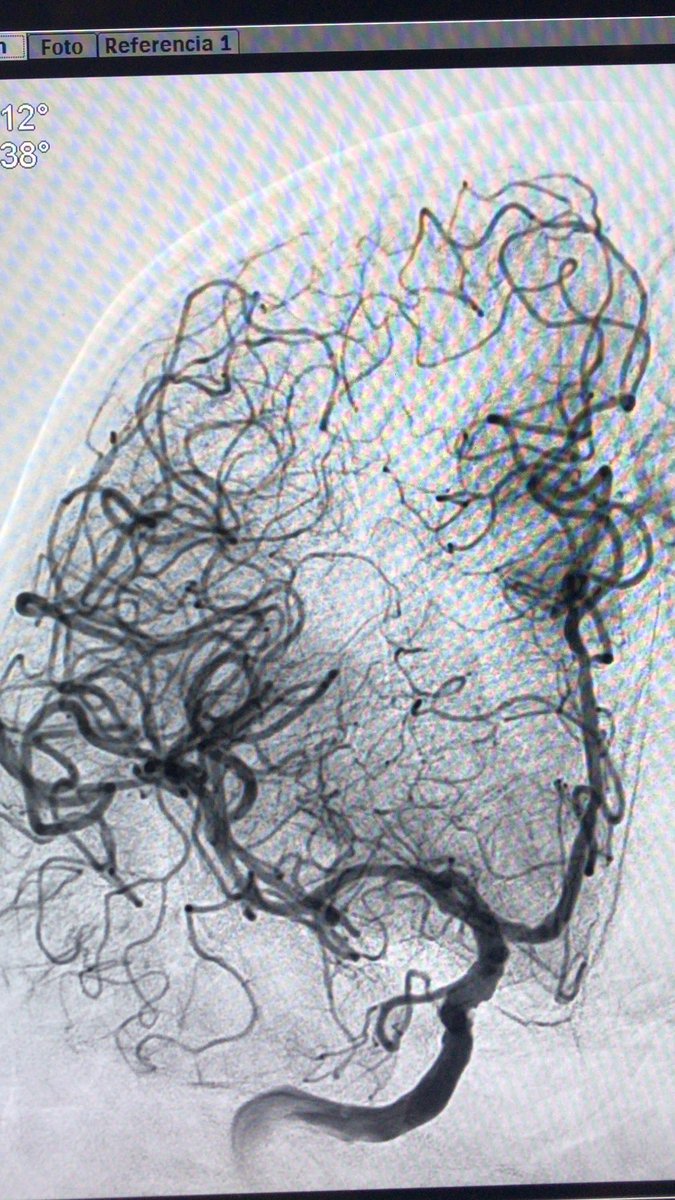

37yo female with SAH Fisher 4.right pcom aneurysm. #RadialFirst #radialforneuro difficulties to get in right carotid>aortography: easy when anatomic variant is understood. Do you see it? Oscar Chirife Sonia Aixut Lorenzo Hospital Universitari Bellvitge | HUB